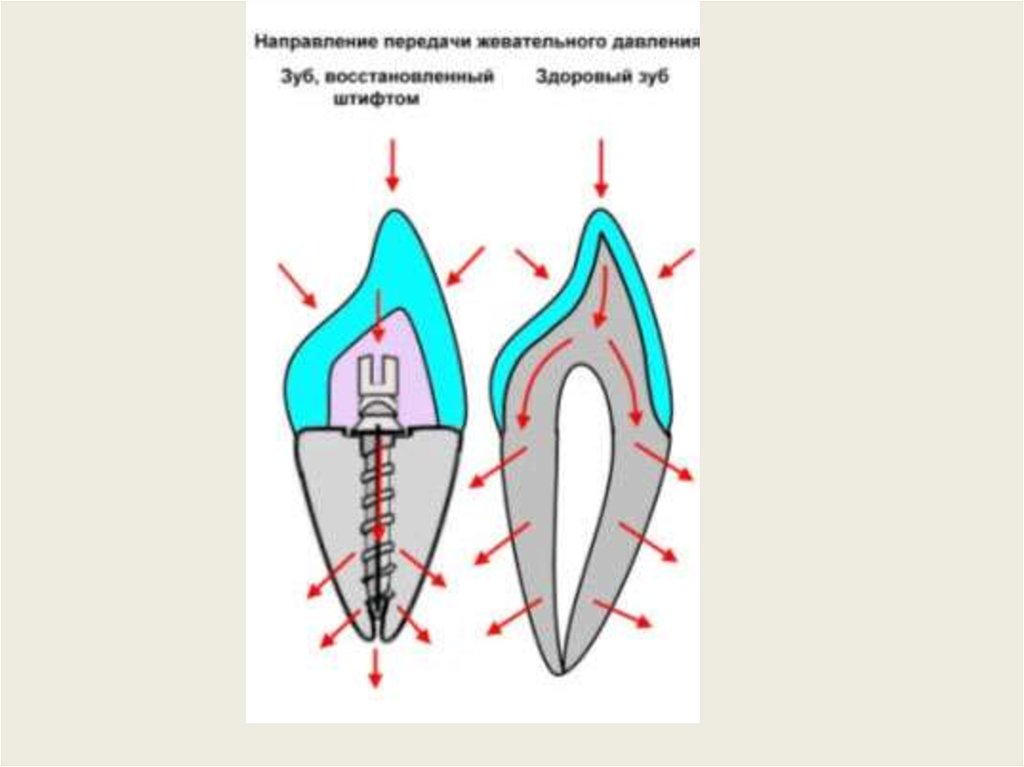

Культя зуба это

Культя зуба это 106 фото